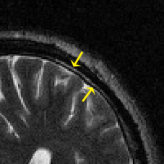

where J1subscript𝐽1J_{1} is the first kind Bessel’s function of order 111. Then using the variable density random sampling method in [46], we generate 20%percent2020\% undersampled k-space data. The complex white Gaussian noise is also added so that the resulting SNR of the samples is approximately 25dB25dB25\mathrm{dB} (See Fig. 3).

Refer to caption

(a) Fully sampled

(b) Ground truth

(c) Sample mask

(d) Undersampled

Figure 3: Dataset for the phantom experiments. Fully sampled k-space data, its inverse DFT as a ground truth, the undersampling mask, and the undersampled k-space data.